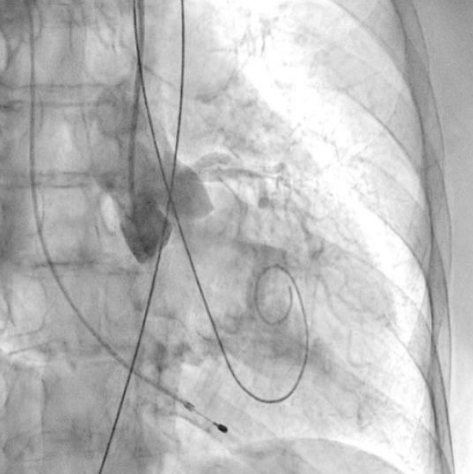

Процедура ТИАК выполнялась по стандартной методике, принятой в нашем центре, за исключением этапа предилатации, который был сознательно пропущен с целью предотвращения развития тяжелой аортальной регургитации (рис. 3-5). Были выполнены позиционирование и прямая имплантация биологического клапана "ACURATE Neo 2" 23 мм, впоследствии дополненная постдилатацией баллонным катетером "Valver" 20×40 мм. На контрольной аортографии: аортальная регургитация 0-1 степени. Коронарные артерии не скомпрометированы, коронарный кровоток удовлетворительный. После выполнения основного этапа операции интродьюсер из правой общей бедренной артерии удален, затем выполнено ушивание места доступа системой зашивающего устройства "ProGlide" (6F) и AngioSeal VIP (8F), наложен кожный шов. Интраоперационно и ранний послеоперационный период протекал без особенностей.

Рис. 3. Пациентка Б. Ангиография корня аорты: визуализируется минимальная регургитация.

Рис. 4. Пациентка Б. Прямая имплантация протеза.

Рис. 5. Пациентка Б. Контрольная аортография.

Во втором клиническом случае был учтен предыдущий опыт и изменена тактика проведения вмешательства у пациентки с аналогичным фенотипом ЛЖ. Исключение этапа баллонной вальвулопластики способствовало снижению риска перегрузки ЛЖ за счет аортальной регургитации. Таким образом, на всех этапах операции у второй пациентки сохранялась разграничительная функция нативного клапана или биопротеза. В третьем клиническом случае у пациентки наблюдался массивный кальциноз АК, что не позволяло исключить этап предилатации. Поэтому было принято решение выполнить щадящую вальвулопластику для обеспечения технической возможности проведения через АК системы доставки протеза. Тем не менее даже умеренная регургитация, появившаяся после этапа предилатации, негативно повлияла на гемодинамику пациентки, которая была скорректирована лишь после имплантации биопротеза. Таким образом, у пациентки удалось избежать выраженной объемной перегрузки ЛЖ, благодаря чему удалось успешно выполнить вмешательство, не прибегая к СЛР.